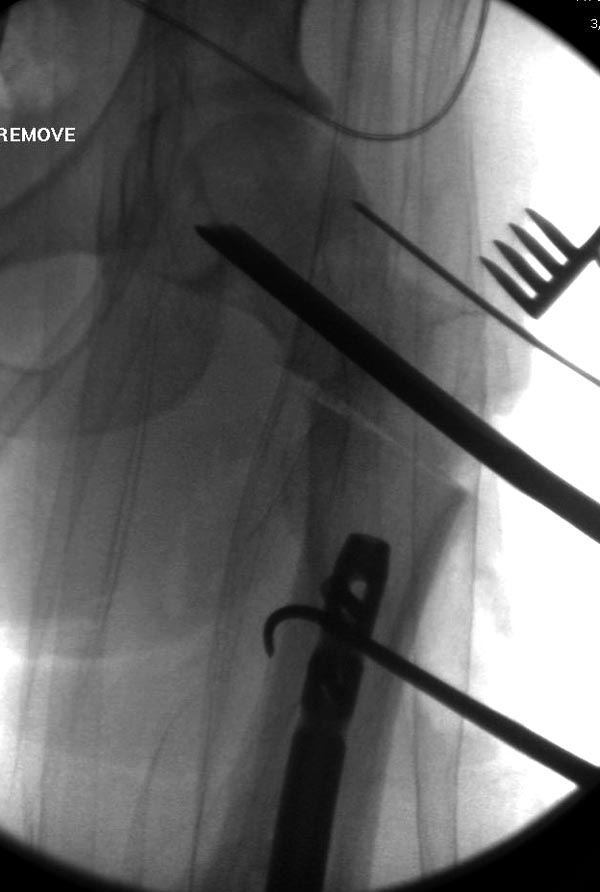

Здесь выставлен ренгенограммы больного, ему 21, травму получил в результате высокоскоростной погони на украденной машине, которая закончилась смертью трех остальных “боевых комрадов”. Начатую коллегой открытую операцию на шейке пришлось закончить мне, установкой винтов и ретроградной фиксацией бедра. Выписка в обычное сроки и наблюдался амбулаторно. Каждый раз напоминали о возможности осложнений ввиде несращения! По истечению 4 месяцев появились признаки варусной деформации. На СТ срезах несращение шейки и бедра. Риминг, замена на более толстый гвоздь и вальгусная остеотомия.

Сразу скажу, что пациент вчера (8.04) прооперирован - артротомия, остеосинтез мыщелков большеберцовой кости канюлированными винтами, открытая репозиция отломков бедренной кости, ретроградный БИОС, остеосинтез надколенника (центральных его отломков) спицами с проволочной петлей. Двухкратная попытка закрытой репозиции шейки на операционном столе после синтеза бедра - абсолютно неэффективна. Учитывая продолжительность и травматичность операции, шейка отложена на 2-й этап. Плечо наверное на 3-й (если вообще делать). Снимки постараюсь предоставить, но чуть позже.